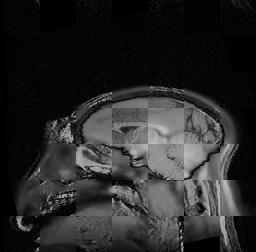

For each of the 10 subjects, we show checkerboard slices in each direction (1) before registration, first row; (2) after rigid->scaleversor->affine registration, second row; and (3) after BSpline registration, third row.

Valentino